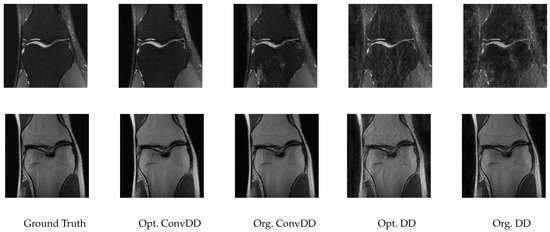

3.7. Accelerated Multi-Coil MRI Data

- Following [7], three additional image comparison metrics are considered along with the PSNR, namely, the Visual Information Fidelity (VIF) [41], Structural Similarity Index (SSIM) [42], and Multi-Scale SSIM (MS-SSIM) [43]. However, following our previous sections, all hyperparameter tuning is done with respect to the PSNR.

- We optimize the same hyperparameters for ConvDecoder as our previous experiments, but the possible settings of filter_size for ConvDecoder during Successive Halving are adjusted as filter_size ∈ [2,3,4,5,6,7], in view of all considered filter sizes being small in [7]. For consistency with [7], we also change the number of optimization iterations to 20,000 for all methods.

- Each scan of a knee from fastMRI consists of a number of slices, each of which is a 2D image, and together the images form a 3D volume. We choose the the middle slice of the volume to obtain each image, and discard the other slices. The train and test sizes are set as 4 and 16, respectively.

| Method | VIF | MS-SSIM | SSIM | PSNR | #Channels | #Layers | Input_Size | Filter_Size | Step_Size |

|---|---|---|---|---|---|---|---|---|---|

| Opt. ConvDD | 0.8212 | 252 | 8 | 5 | 3 | 0.002 | |||

| Org. ConvDD | 0.9599 | 0.9422 | 31.0642 | 256 | 8 | 4 | 3 | 0.008 | |

| Opt. DD | 0.6021 | 0.8204 | 0.6515 | 28.2947 | 352 | 9 | 18 | - | 0.002 |

| Org. DD | 0.5725 | 0.8029 | 0.6529 | 28.2217 | 368 | 10 | 16 | - | 0.008 |

| Org. DIP | 0.5644 | 0.8644 | 0.5163 | 26.9310 | 256 | 16 | (640,368) | 3 | 0.008 |